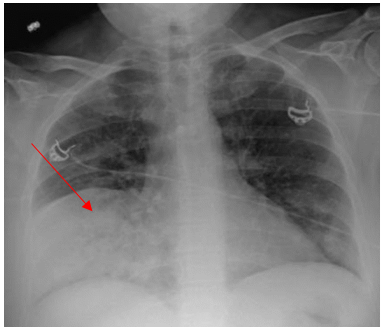

A 52-year-old Caucasian female, who is a resident of southwestern Ohio, presented to the emergency room with a chief complaint of a two-week history of right-sided chest pain, which had progressively worsened despite two courses of antibiotics and pain medications following her two recent visits to the emergency department. She also described subjective fever, shortness of breath, nonproductive cough and weight loss of 4 kg over the last two weeks. She was a smoker of ½ pack per day for 20 years and quit smoking 4 weeks ago. The patient’s past medical history includes anxiety, depression, gastroesophageal reflux disease, hypertension, mitral valve prolapse, and migraine headache. Her chest pain started in early September, and it was described as stabbing and pleuritic, which was also noted to be reproducible to palpation of the chest wall. She was seen first at the emergency department two weeks prior to the current presentation for evaluation of the right-sided chest pain. Still, at that time, there was no fever or cough, and her vitals were stable with Oxygen Saturation 94% on room air, although her laboratory testing was significant for leukocytosis with (WBC):16.6 K/UL with 68.5% neutrophils. Chest-X-ray demonstrated an infiltrate in the right lung base medially, while CT–chest angiography demonstrated no evidence of pulmonary embolism and right middle lobe consolidation consistent with pneumonia. There was no mediastinal or hilar lymphadenopathy, (Figures 1 and 2).

Figure 1. Portable Chest X-ray showing infiltrate in right lung base medially.